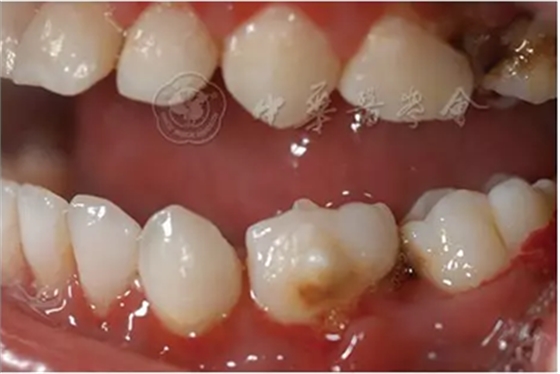

(1)疾病定義及口腔表現(xiàn):中性粒細胞減少是由于外周血中粒細胞的絕對值減少而出現(xiàn)的一組綜合征。出生后2周至1歲的嬰幼兒中性粒細胞低于1×109/L、1歲以上兒童中性粒細胞低于1.5×109/L時,即可診斷為中性粒細胞減少癥。當中性粒細胞低于0.5×109/L時則可診斷為粒細胞缺乏(agranulocytosis)。根據(jù)中性粒細胞減少的程度和持續(xù)時間,病情的輕重不同。病程初期為發(fā)熱,之后表現(xiàn)為反復感染且難以控制,好發(fā)于呼吸道、泌尿系、皮膚和黏膜等。在口腔主要表現(xiàn)為反復發(fā)作的口腔炎、口腔潰瘍,牙齒松動、乳牙早失,牙齦紅腫、糜爛、齦袋溢膿及牙槽骨喪失等(圖1)。

圖1 4歲中性粒細胞減少患兒乳牙牙齦明顯紅腫、糜爛